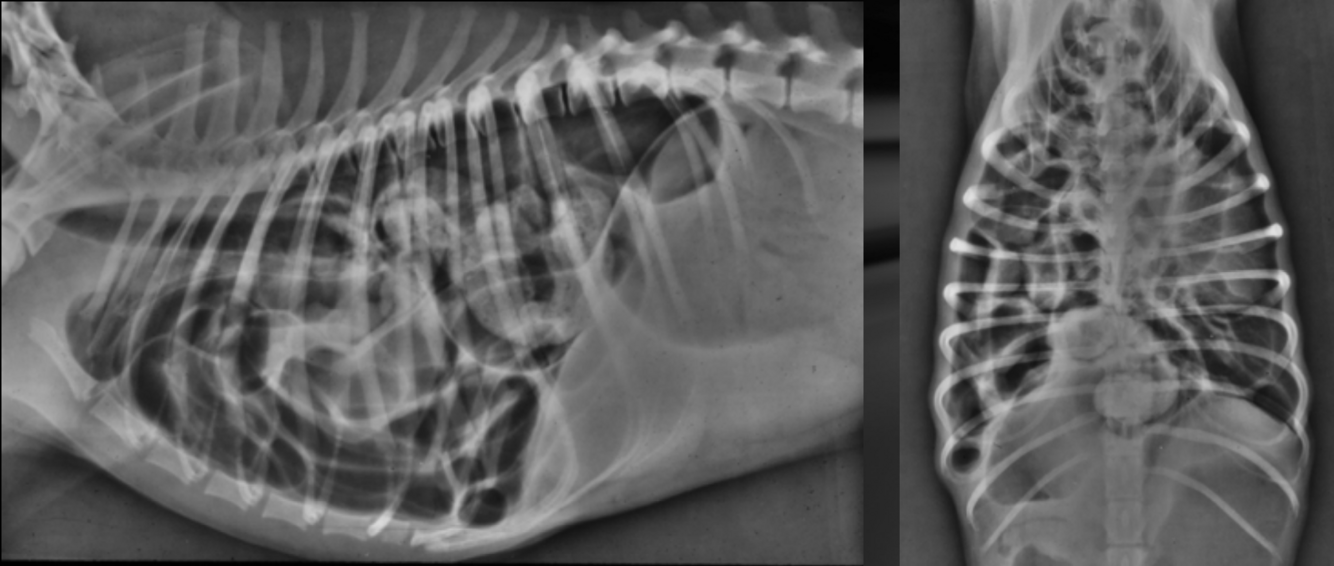

What is important regarding the ribs in these radiographs?

old dog; costal cartilages show irregular, exuberant mineralization